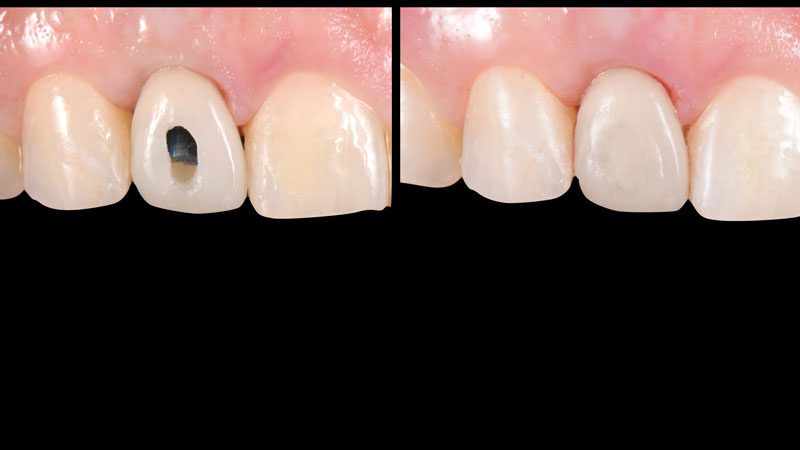

Hình 9. 3 tháng sau khi cắm Implant, chú ý cấu trúc mô mềm xung quanh vẫn còn nguyên.

Hình 10. Lấy dấu bằng coping cá nhân để ghi lại cấu trúc mô mềm và chuyển qua mẫu hàm cho chính xác.

Hình 11. Phục hình tạm lưu giữ bằng ốc vặn.

Hình 12. Phục hình tạm trên mẫu hàm.

Hình 13. Phục hình tạm sau khi gắn trong miệng. Lỗ vặn được bít lại bằng Teflon (cao su non) và phủ composite lên.